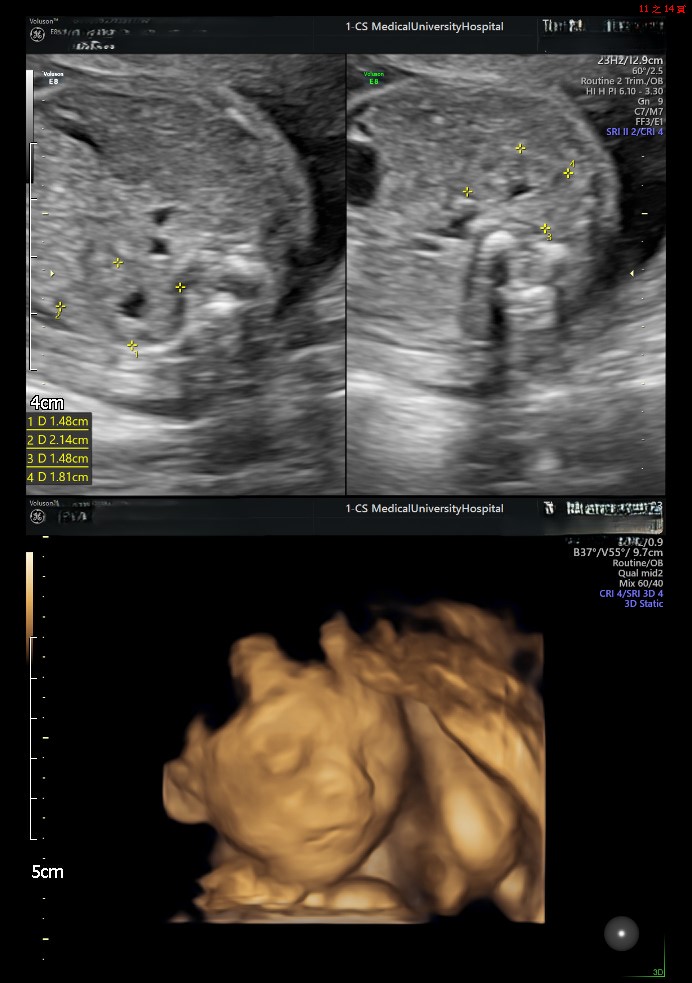

小美決定尋求幫助, 於是來到了我們的中山醫學大學附設醫院生殖醫學中心。經過詳細的檢查,我們發現了小美子宮內膜息肉以及維生素D缺乏, 這些是影響她懷孕的關鍵因素。

後來,我們為她制定了客製化的治療計劃,包括息肉切除手術和維生素D補充來進行卵子培養。 手術後,小美感覺到生活慢慢回到正軌。